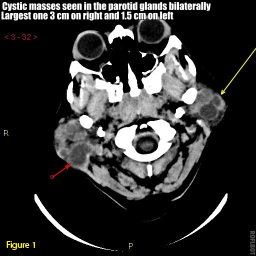

CT scan and MRI of the head and neck showed normal midline structures. Multiple masses were seen bilaterally in the parotid glands; the largest mass on the right side measured 3 cm; the largest on the left measured 1.2 cm (Figures 1 and 2).